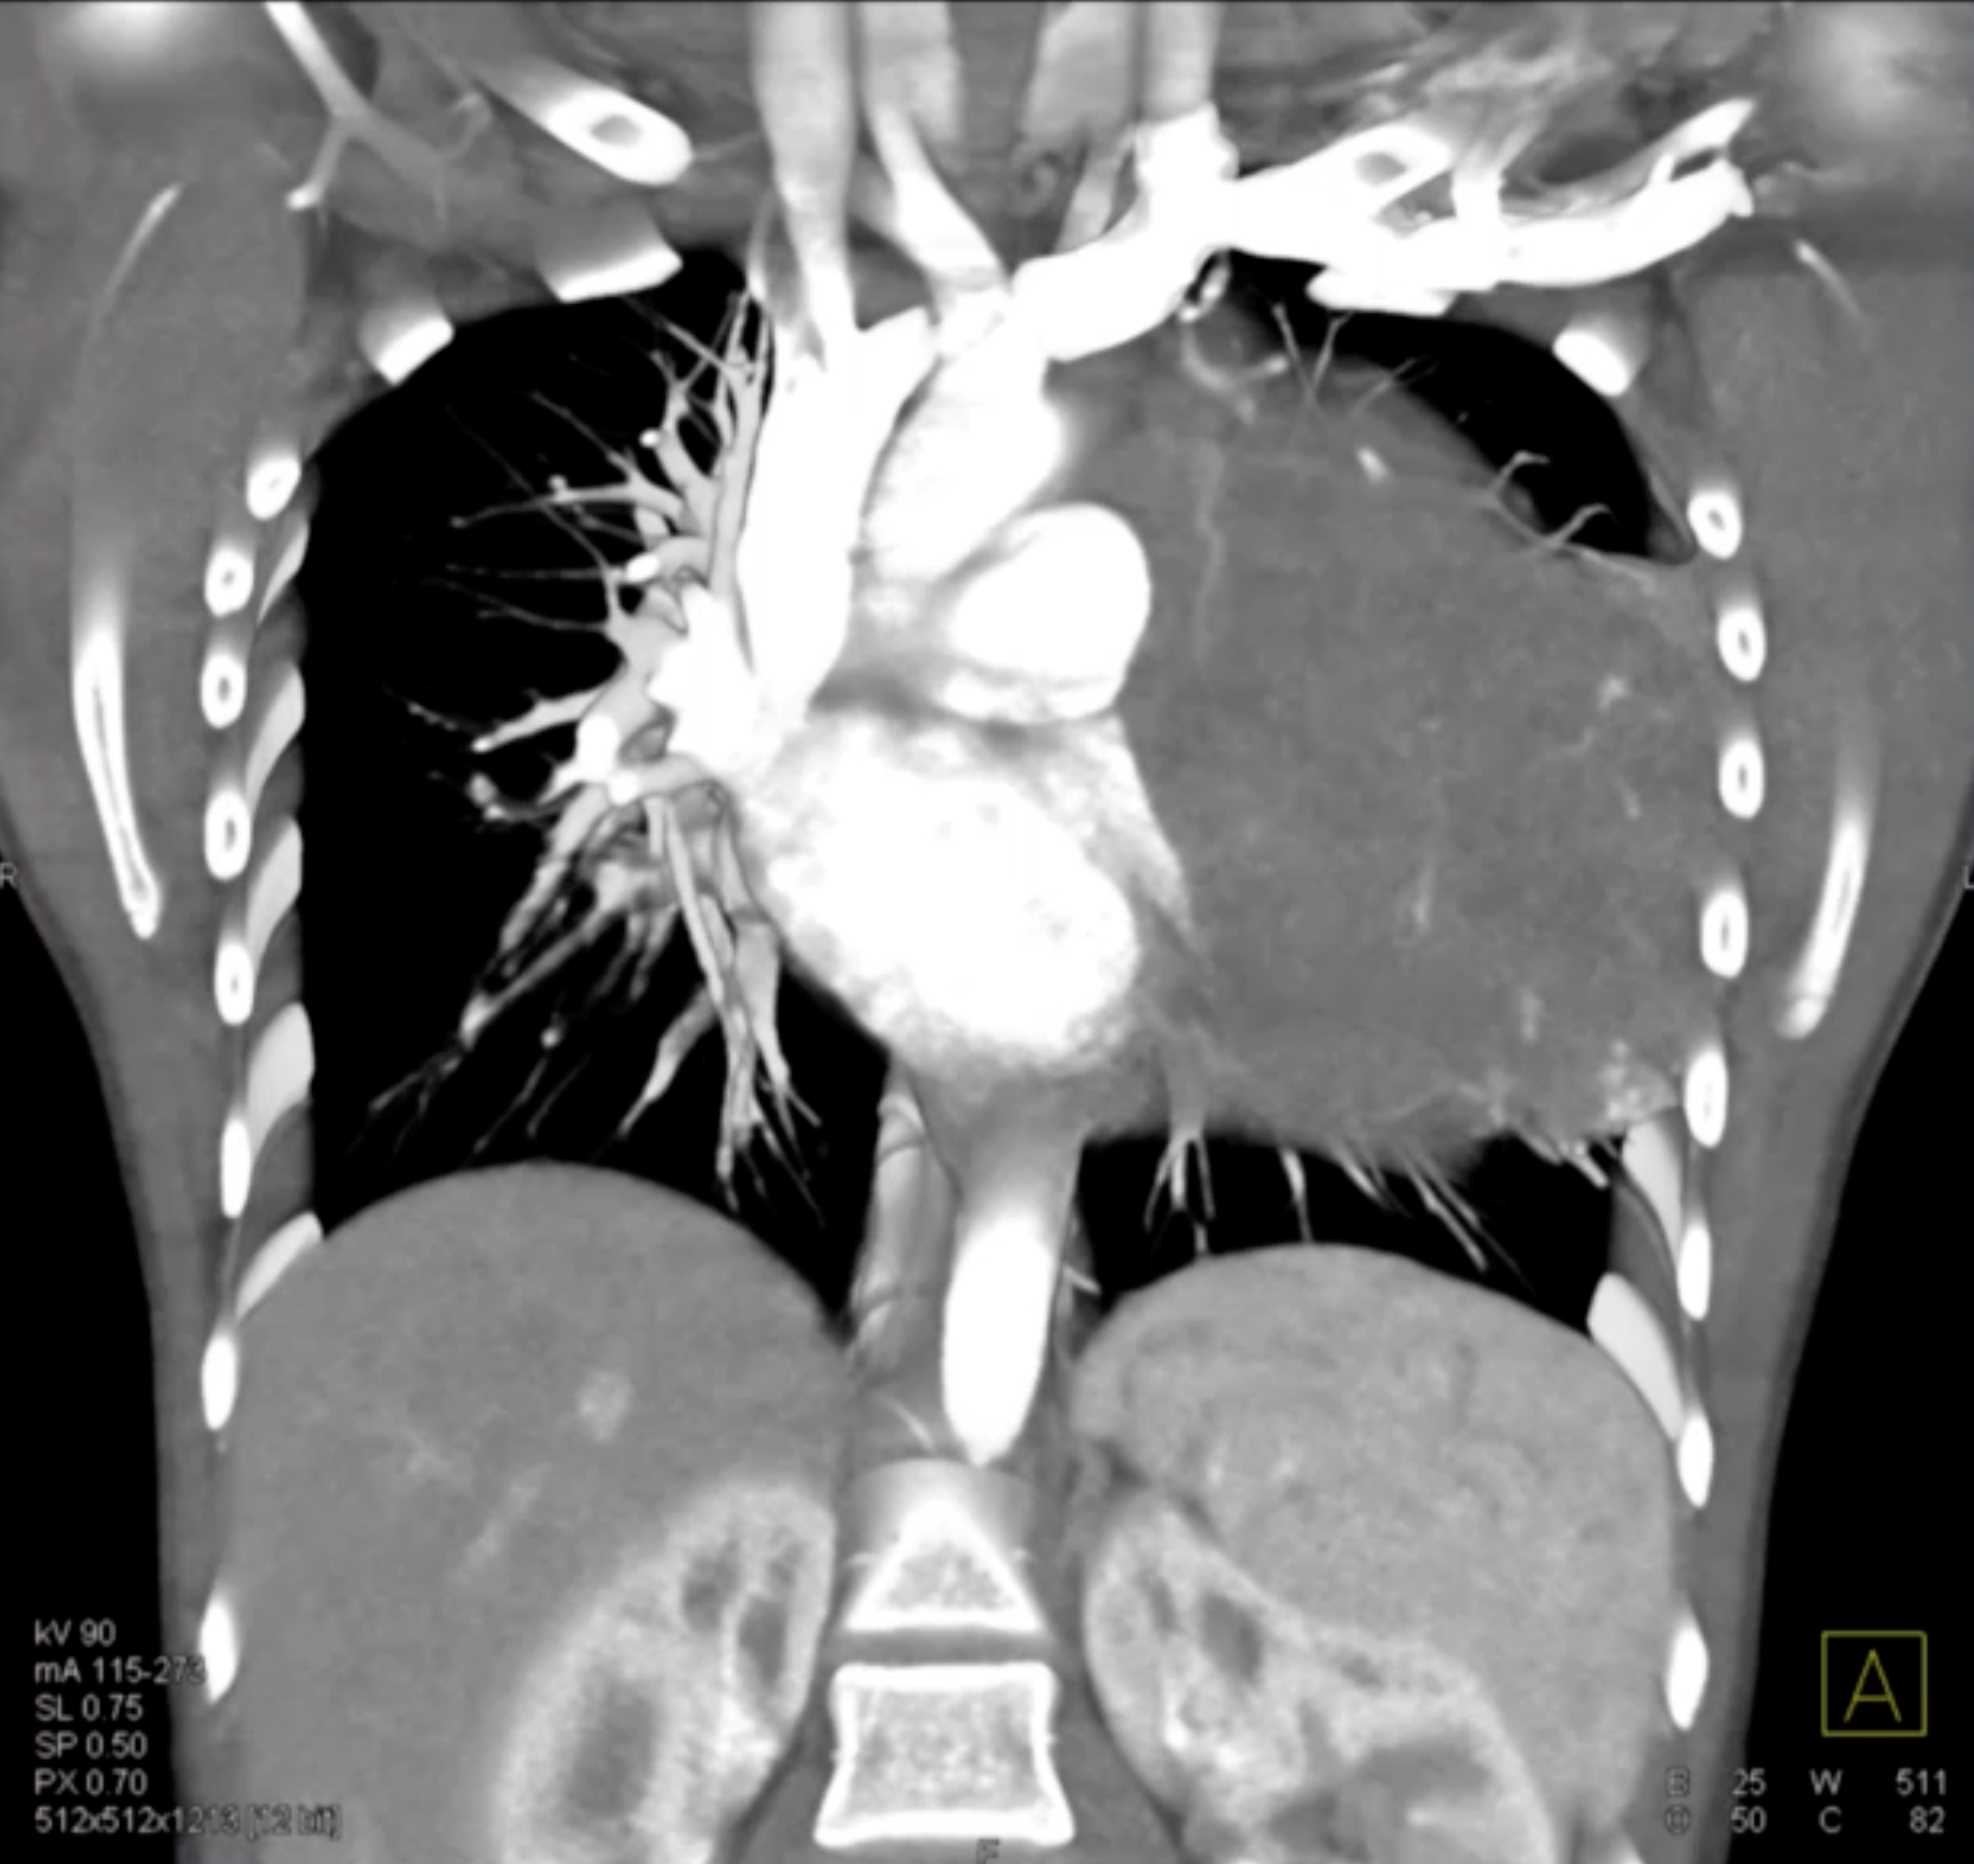

Subtle Adenocarcinoma Pancreas